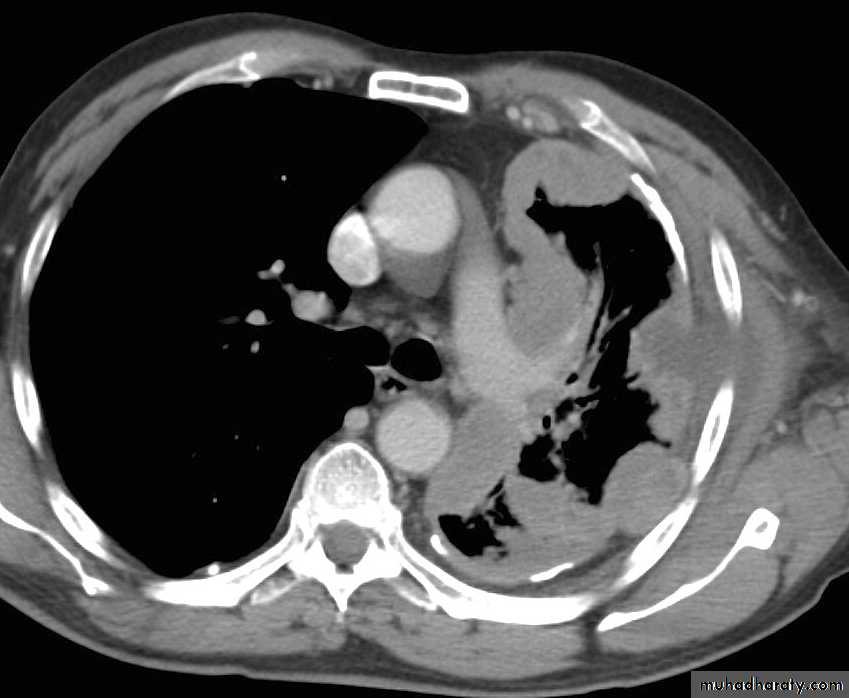

What is the difference??CT scan

• CT scan

CXR: